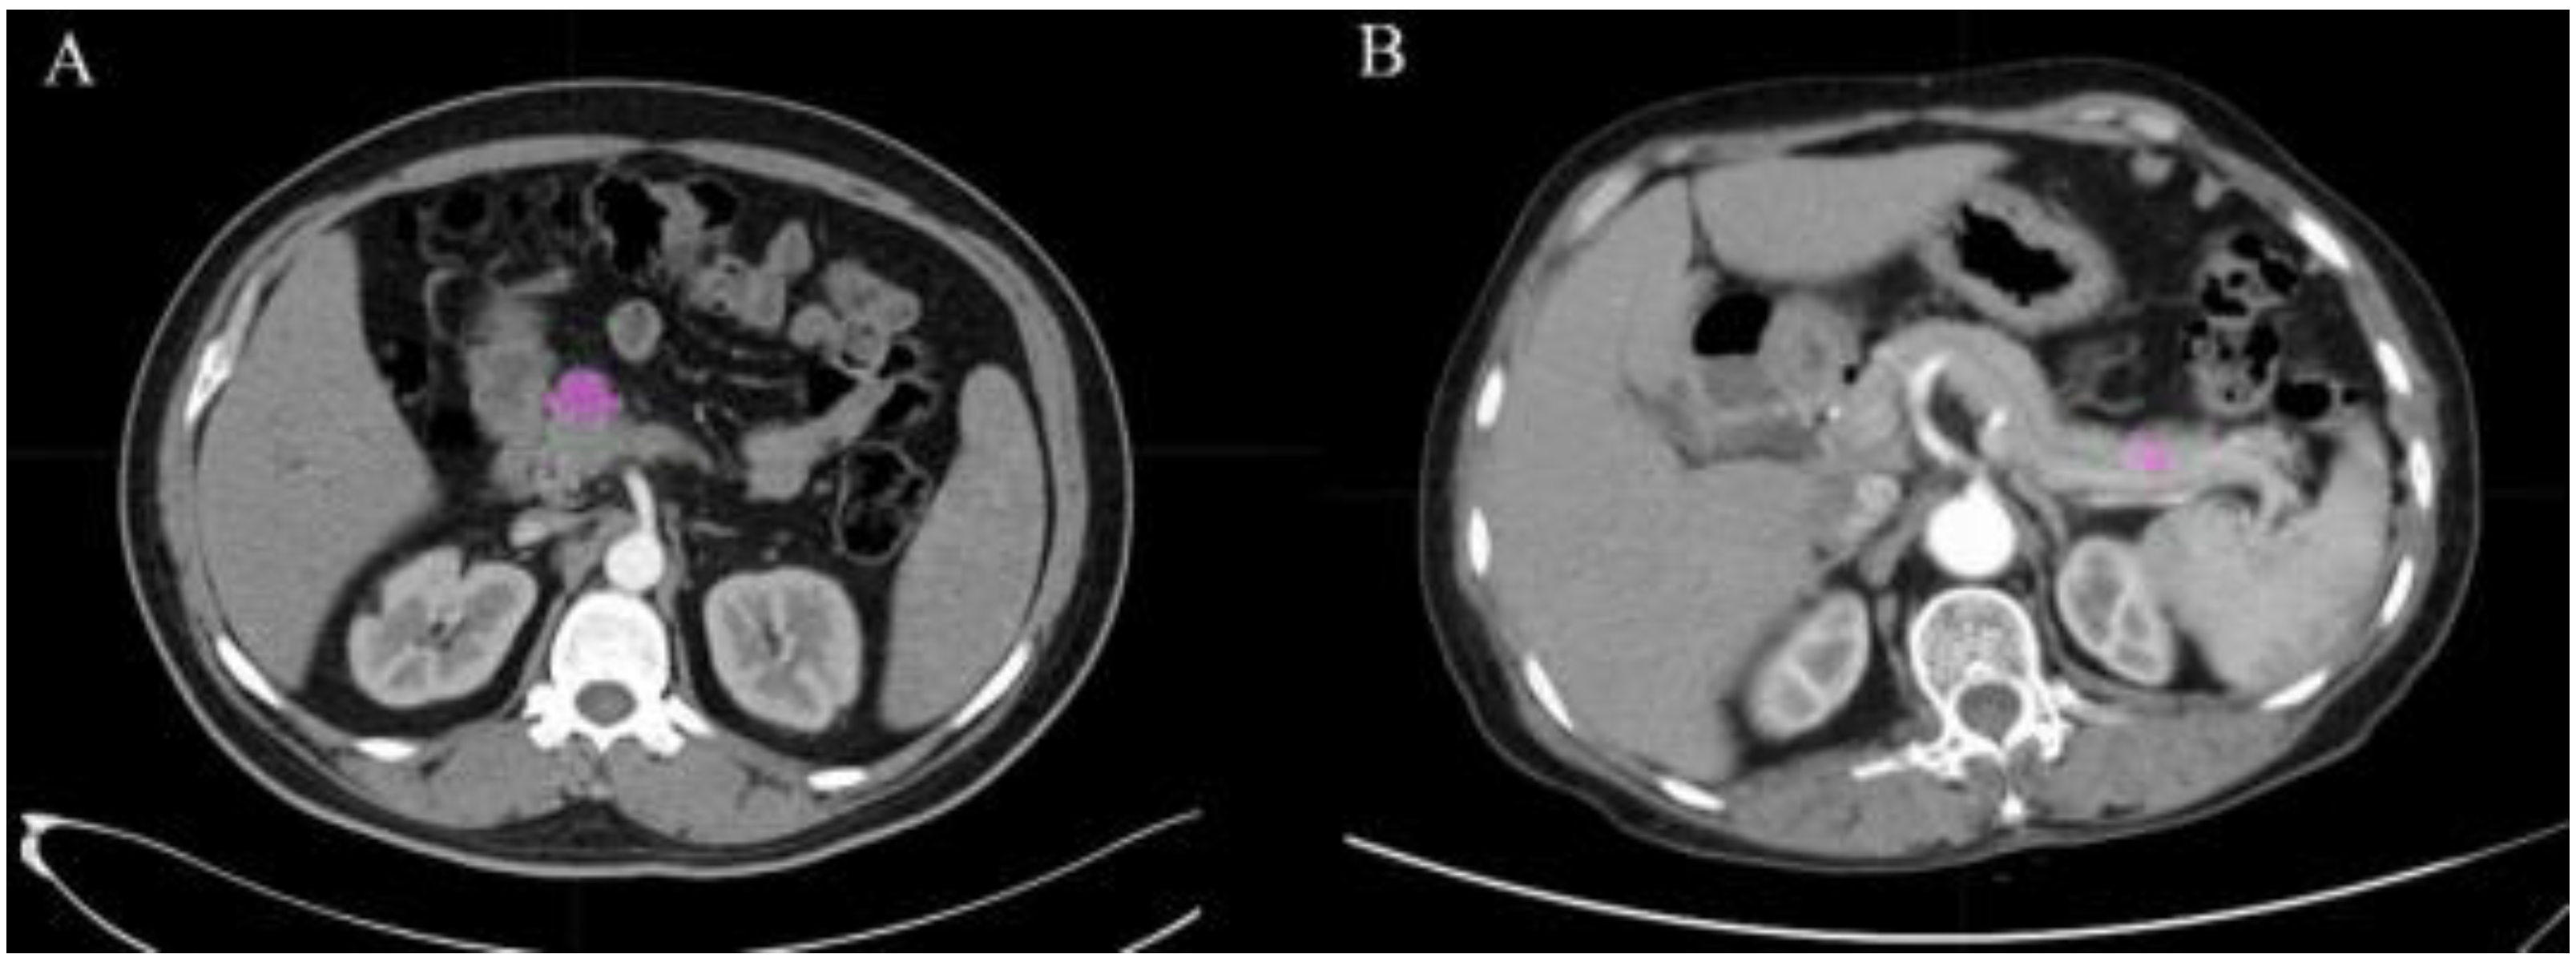

2.2. Image Acquisition and Texture Feature Extraction